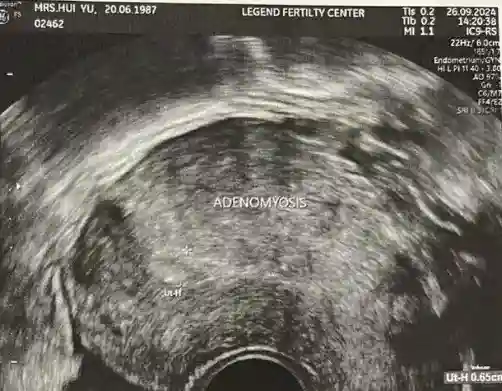

▫️患有子宫腺肌症 / 瘢痕憩室 / 宫腔息肉

1️⃣ 复杂子宫环境影响胚胎着床